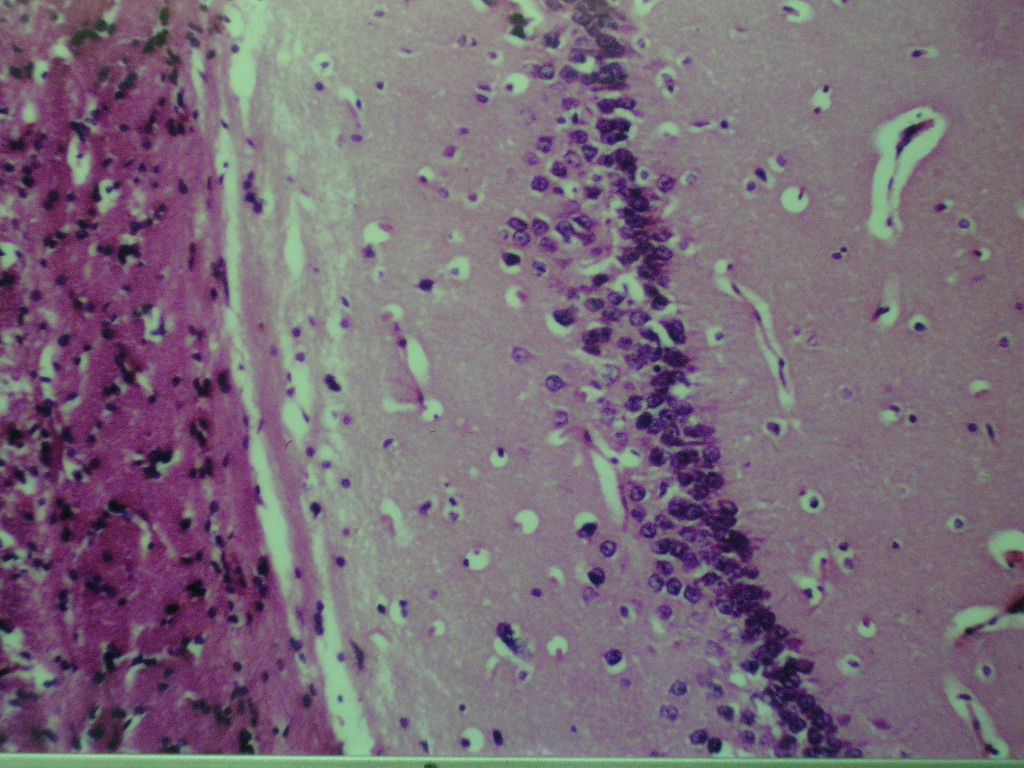

Fig (1): Micrograph of brain section of normal control rat showing normal morphological structure of the hippocampus (H& E X40). Fig (2): Micrograph of brain section of ovariectomized control rats showing normal morphological structure of the hippocampus (H& E X 40). Fig (3): Micrograph of brain section of Al-intoxicated ovariectomized (AD group) rats showing various sizes of amyloid plaques formation (arrow) in the cerebral cortex and hippocampus (H& E X 40). Fig (4): Micrograph of brain section of AD rats treated with α-chymotrypcin in a dose of (8.1 unit/rat/day) showed the presence of focal gliosis in the cerebrum and disappearance of most of amyloid plaques.

Fig. 1: Micrograph of brain section of normal control rat showing normal morphological structure of the hippocampus (H& E X40)

Fig. 2: Micrograph of brain section of ovariectomized control rat showing normal morphological structure of the hippocampus

(H& E X 40).

Fig. 3: Micrograph of brain section of Al-intoxicated ovariectomized (AD group) rat showing various sizes of amyloid plaques formation (arrow) in the cerebral cortex and hippocampus (H& E X 40).

Fig. 4: Micrograph of brain Section of AD rats treated with α-chymotrypcin in a dose of (8.1 unit/rat/day) showed the presence of focal gliosis in the cerebrum associated with the disappearance of most of amyloid plaques.